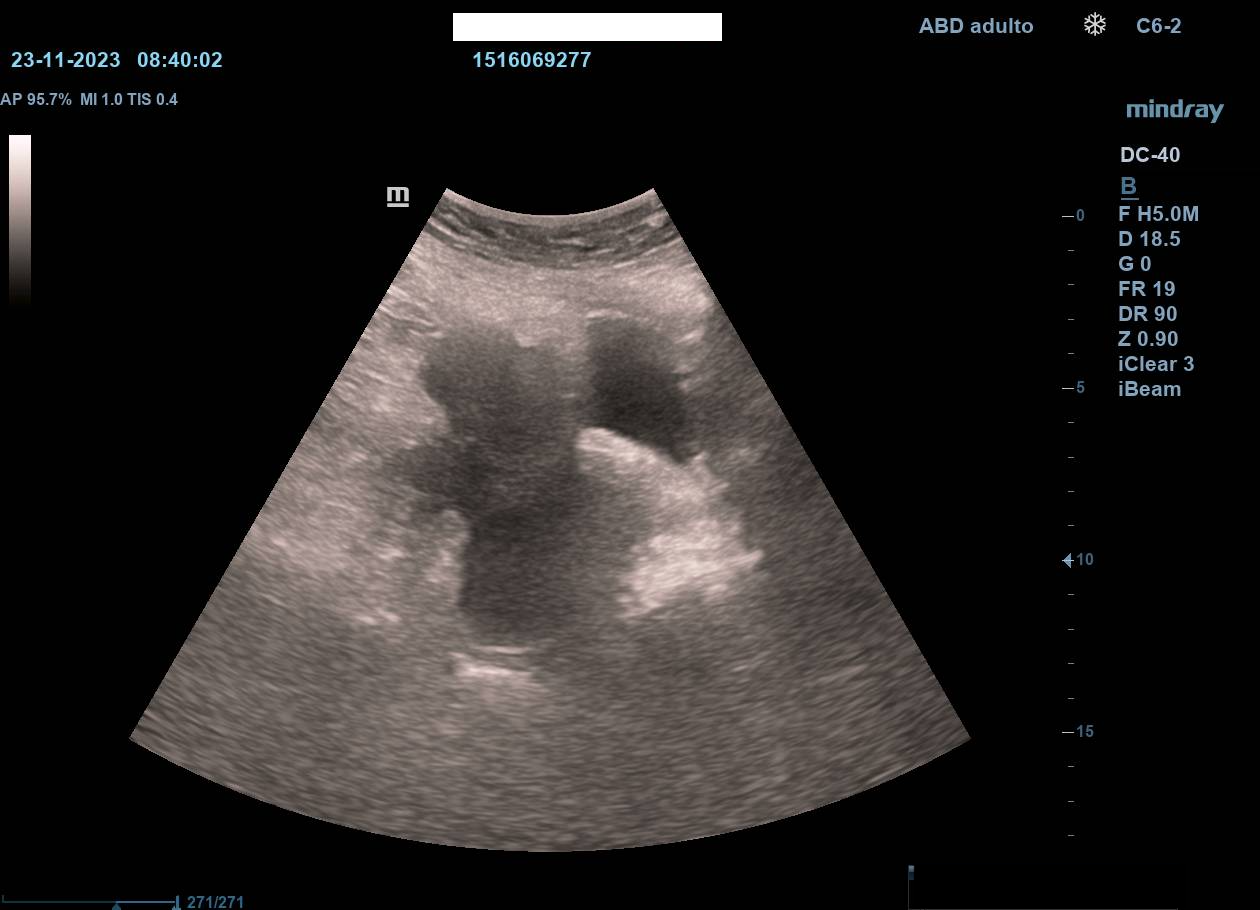

Hallazgos ecográficos

La ecografía en atención primaria permitió un abordaje inicial inmediato, objetivándose dilatación de asas intestinales en la zona de la tumoración, sospecha de ascitis y no visualización de riñón izquierdo (atrofia previa). Estos hallazgos, junto con la exploración, motivaron derivación urgente a Medicina Interna con sospecha de tumoración abdominal.